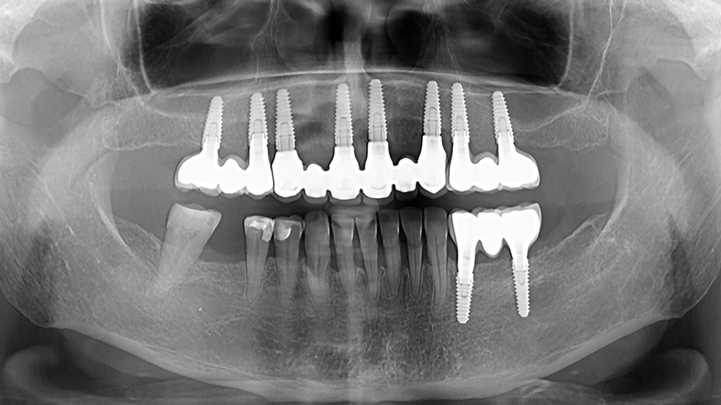

Clinical case: Advantage of fuse abutment with AnyRidge implant for immediate loading in

upper fully edentulous case

“AnyRidge shows excellent initial stability

& stable results after immediate loading in

upper fully edentulous case. ”

Clinical case: Extraction of all teeth in upper maxilla,

immediate implant placement, & provisionalization

- Courtesy of Dr. Iulian Filipov, Romania -